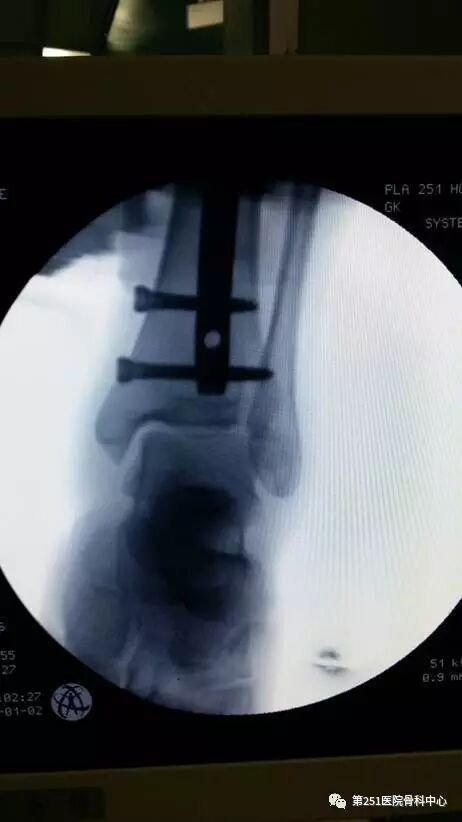

病例6:男性,39岁,车祸伤SchatzkerⅥ型胫骨平台骨折。

![]()